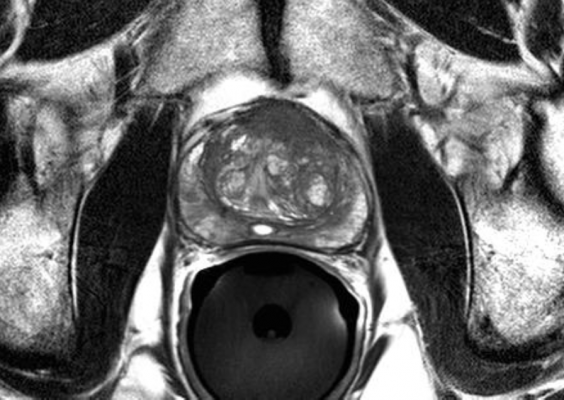

Focal therapy is a technique of treating only the cancerous areas of the prostate, not affecting the rest of the prostate. The focal therapy program at Mount Sinai will be the first to use fusion biopsy technology to deliver treatment more precisely. Fusion-guided biopsy, an imaging technique which combines magnetic resonance (MRI) and ultrasound imaging to better visualize the prostate during procedures, has been in use at Mount Sinai since 2013 for obtaining biopsy samples.